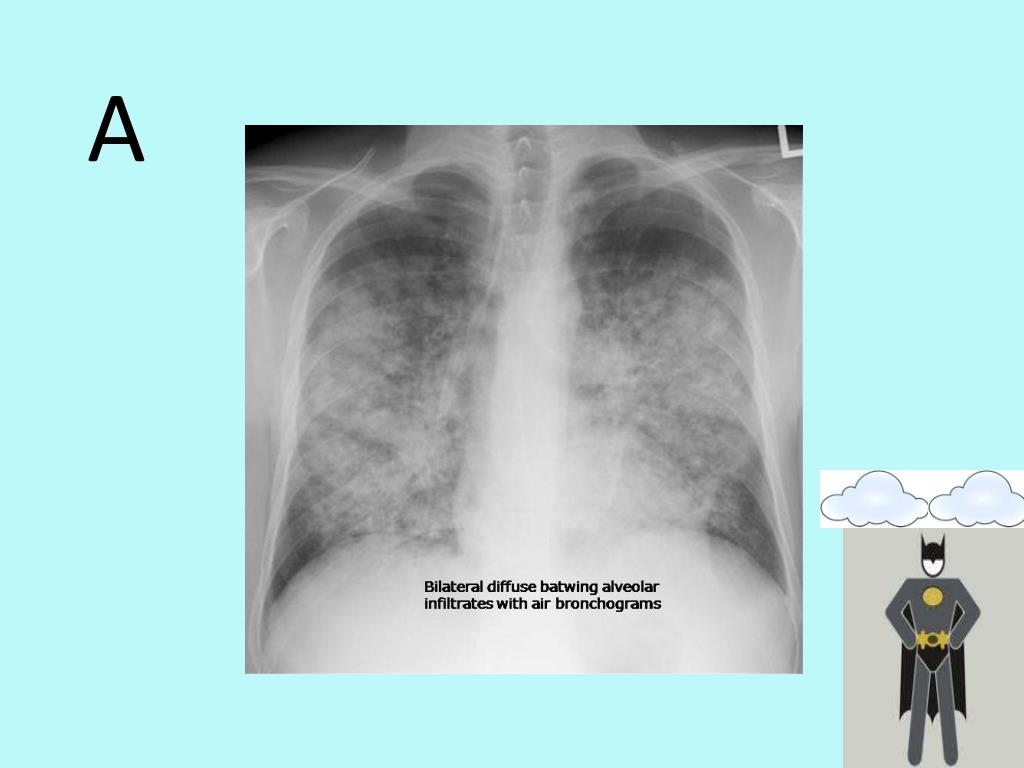

9. CXR findings • A- alveolar oedema • B- KerleyB lines • C- cardiomegaly • D- diversion to the upper lobes • E- pleural effusion (bilateral)/pulmonary oedema

10. A